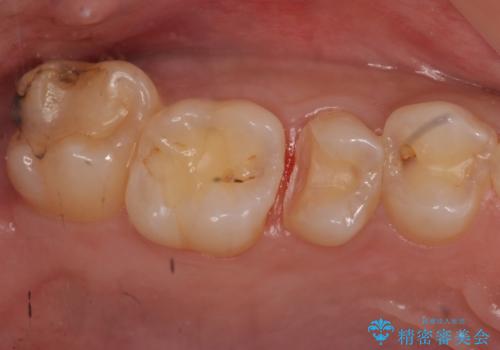

- 右上5 セラミックインレー 77000円×1本費用は治療当時の料金となります

局所的に深い虫歯が確認されましたが、神経は温存することができました。

歯と歯の間から広がる虫歯は目視では確認しにくいため、定期的にチェックし悪化を予防することが大事です。